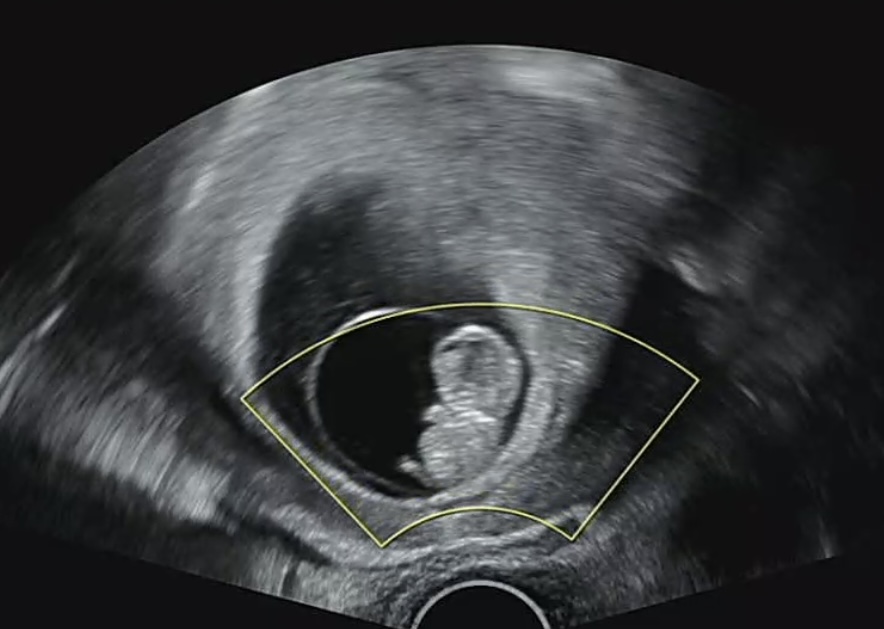

| 가슴 떨리는 임신 이야기를 공유해 주세요. | 내 인생에 겪으리라 상상해보지 못했던 일들을 마주하고 수없이 절망하고 현실을 외면하고 나름 서로 애써 위로하며 무수한 현실 속 많은 이야기들에 무뎌짐을 경험하면서 1년이란 시간을 보내고 결국 우리에겐 아이가 필요하다는 것을 깨닫고 아이비에프에 첫 발을 내딛게 되었습니다. 그러고도 6개월을 주저하다 12월에 원장님을 다시 찾아뵙게 되었네요. '드디어 오셨네요' 라는 원장님의 첫마디가 아직도 뇌리에 깊게 박혀있어요 그리고 그로부터 6개월이 지난 지금 저는 10주 임산부가 되어있습니다. 믿기지 않는 하루 하루를 보내고 초음파을 볼때마다 처음 느껴보는 감정들과 설렘을 느끼며 우리의 오랜 고민 끝에 닿은 결정이 결코 틀린 결정이 아니었음을 깊히 느끼고 깨닫는 중입니다. |

| 치료 도중 느꼈던 가장 기뻤던 순간과 절망적인 것들은 무엇인가요? 잊지 못할 경험이 있나요? | 누구나 그렇듯 가장 기뻤던 일은 테스트기 2줄, 아기집, 그리고 아기가 벌써 팔다리가 생겨 꼬물거림을 보았을때가 아닌가 싶습니다. 생각보다 어렵지 않았던 시험관 진행이었지만, pgt 두번째에도 통배가 안나왔을때 정말 펑펑 울었던 것 같아요 왜 우리는 이렇게 힘들게 아기를 가져야만 하는건지 하며 오랜만에 또다시 절망속에 빠진듯한 기분이었습니다 그리고 원장님과 긴 상의끝에 기존 모자이시즘 배아를 이식하게 되었고 이식 1차만에 로또 아기를 품게되었어요 심장소리 듣기 전까지는 온 신경이 집중되고 정말 조마조마 했던 것 같습니다 심장소리 한 세번 듣고 나니 이제는 조금 마음이 편해졌어요 |